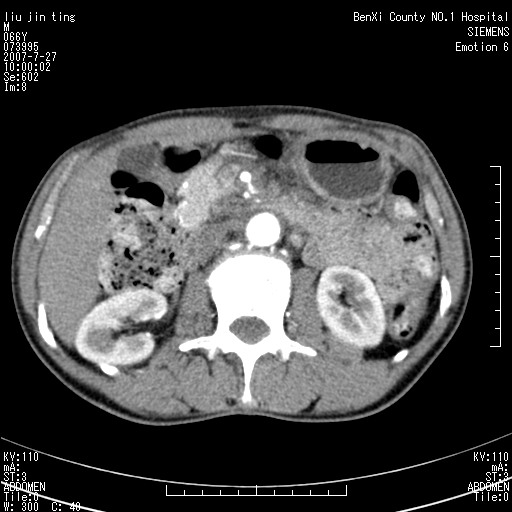

腹痛,背痛,无恶心呕吐,不黄,彩超示胰腺钩癌,ct扫描病灶平扫30-40hu,增强后动脉期40--60hu,静脉期50-68hu,真的是钩突上的么?您要试一试么?

动脉期

静脉期

沿着肠系膜上动脉呈匍匐性生长的软组织肿块,形态不规则,包绕肠系膜上动脉,呈明显强化,考虑来源于肠系膜的恶性肿瘤

沿着肠系膜上动脉呈匍匐性生长的软组织肿块,形态不规则,包绕肠系膜上动脉,呈轻-中度强化,考虑来源于肠系膜的恶性肿瘤。

钩突是正常的,只见腹膜后淋巴结的肿大,考虑淋巴瘤或转移可能。